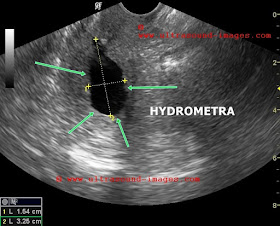

This elderly patient shows an anechoic fluid collection in the endometrial cavity or hydrometra.

Large collections such as these are usually caused by cervical canal stenosis or cervical mass lesions.